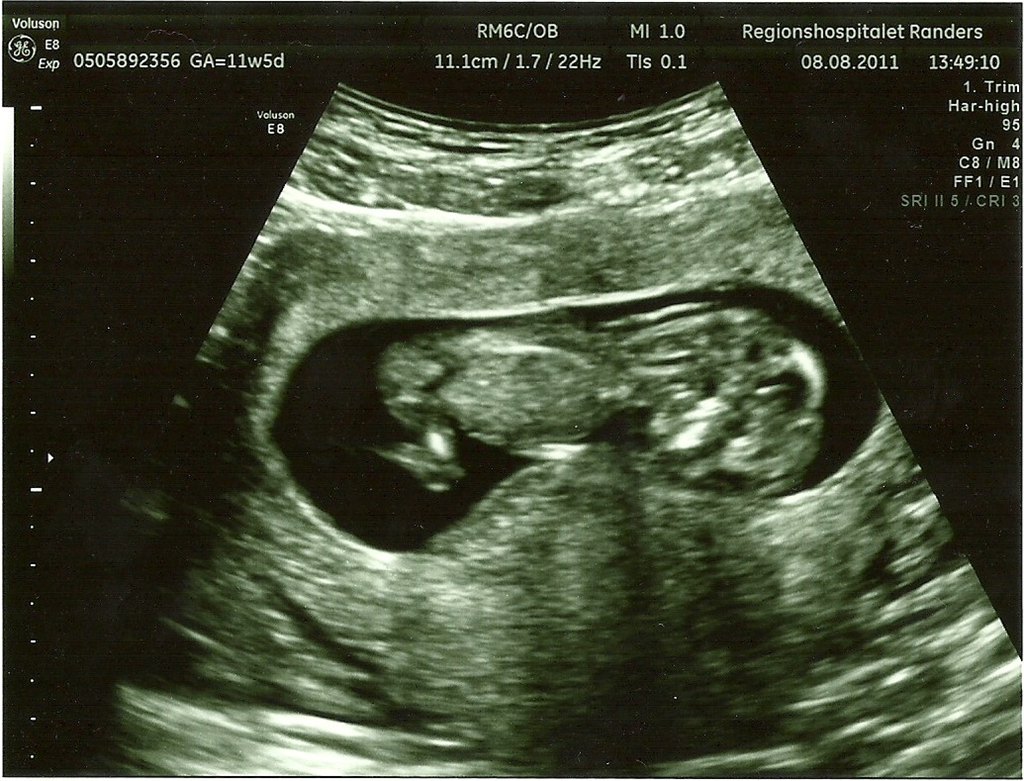

Ja så var det endelig tid til NF - alt så fint ud og det var et MEGET aktivt lille væsen der gemmer sig derinde - mere stolt kan man ikke være og storsøster syntes det er så sejt at vi nu har billeder af babyen!

På billedet med numsen i vejret